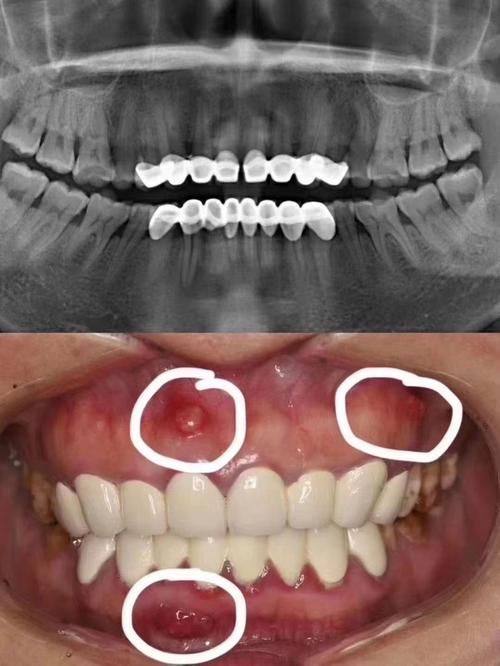

牙齿缺损可能是由于外伤、龋齿等原因造成的。牙齿一旦缺损,不仅影响美观,还可能导致食物残渣容易残留,引发其他口腔问题。烤瓷牙在牙齿缺损的修复上有独特的优势。对于较小的牙齿缺损,烤瓷牙可以精细地修复缺损部分,修复牙齿的原有形状。它可以根据牙齿的颜色进行调色,使修复后的牙齿与周围真牙颜色一致,达到自然美观的成效。

如果牙齿缺损较大,但牙根还比较健康,也可以通过烤瓷牙进行修复。医生会先对牙根进行处理,然后制作合适的烤瓷牙冠套在上面。这样既能保留牙根,又能让牙齿修复正常的外观和功能。而且烤瓷牙的强度较高,能够承受一定的咀嚼压力,在日常生活中可以正常使用。